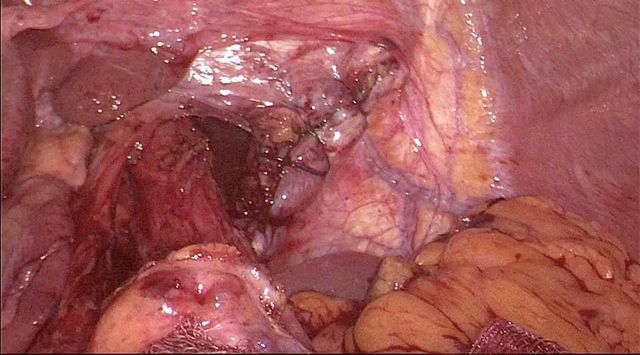

Case of post cholecystectomy biliary stricture with complete cutoff and external biliary fistula

Interesting images December: Case of post cholecystectomy biliary stricture with complete cutoff and external biliary fistula. Pt was 6 months after injury He was refused surgery elsewhere and told to wait for fistula to close as there was no biliary dilatation. After a complete cutoff the the external biliary fistula mostly closes over a period of time by fistulizing into duodenum. However after 2- 3 month waiting period presence of a persisting fistula there is no need to wait forever. By the hepp- couinad approach the anastomosis is a side to side anastomosis to the extrahepatic left duct which is abt 3-4 cm in length and as you can see in the images despite the apparent lack of dilatation on MRCP we could achieve a wide 3 cm side to side anastomosis to the confluence and left duct. The anastomosis is by a standard parachuting blumgart kelly technique. The lack of biliary dilatation is not a contraindication to reconstructive surgery after BDI after an adequate waiting period.